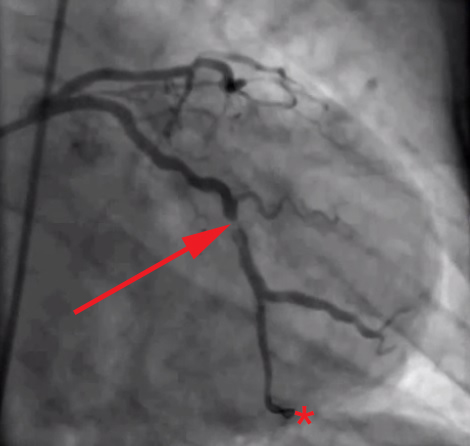

アイキャッチ画像